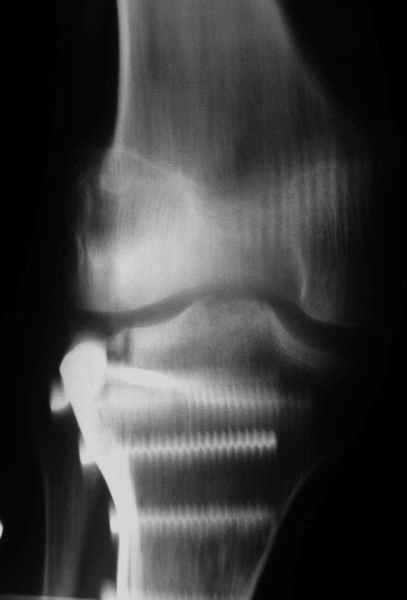

Относительно "рубцовой подушки" я имел в виду остатки мениска ( частично вколоченного в дефект мыщелка и фрагменты хряща), все таки на рентгенограммах суставная щель в этом отделе чем то заполнена. Что касается некроза мыщелка бедра, то мне кажется он уже наступил - томограмма ноябрь5.

С учетом всего сказанного - наличия прогессирующего вальгуса конечности, довольно приличного объема движений, имеющегося, вероятно, некроза мыщелка бедра, наиболее рациональным представляется удалить пластину с б\б кости, произвести остеотомию б\б кости с коррекцией вальгуса, разгрузив тем самым наружный отдел сустава, и синтезировать фрагменты голени накостным фиксатором. Максимально тано начать восстановление движений в суставе. Скорее всего рано или поздно речь о протезировании всеже возникнет, но мы хотя бы будем иметь приличную ось конечности.

С *вколоченным* мениском встречаться не приходилось, нередко при импрессионных переломах наблюдал центральную дислокацию мениска по типу bucket handle, что в этой ситуации может объяснить сгибание сустава до 90 и разгибание 160 градусов, отчасти невозможность полностью разогнуть ногу при Рг графии сустава затрудняет интерпретацию прямой проекции сустава.

Сканирование с Тс99 поможет верифицировать наличие некроза мыщелка бедра, если использовались титановые винты, то магнитно-резонансное исследование будет более информативным. При подтверждении некроза, бедренная или всокая тибиальная остеотомии, очевидно, будут малоуспешны, поэтому альтернатив артропластике похоже не останется. Наблюдений реваскуляризации мыщелка бедра после туннелизации у меня нет, надо покопаться в литературе.